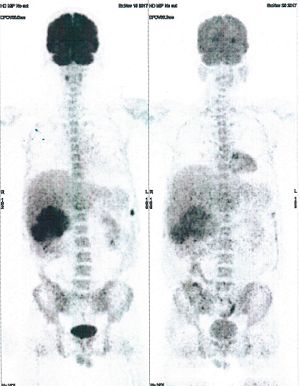

Below are some of the cases, from more than 80 cases we have treated so far with good results. When reading the PET/CT scans, the picture on the left is before treatment, and the picture on the right is after treatment. The intensity of black represents the activity of the cancer, but some black areas are not cancer: brain, heart, radioactive urine in bladder. For the heart, the intensity of black depends on the number of hours of fasting: if more than 10 hours, the heart is not even black, but if fasting is less than 6 hours, it is very black. The intensity of black in the brain can be variable in different scans depending on the brain activity at the time of the scan. The intensity of black in the radioactive urine can also be variable due to the hydration of patients and the time of injection of diuretic.

CASE NO: 1

(HEPATOCELLULAR CARCINOMA + STOMACH CANCER)

A middle-aged women who is very thin and very weak, can hardly walk, lying in bed most of the time. She saw a cancer specialist in a top hospital who discovered that she had massive hepatocellular carcinoma, and another cancer in the stomach. Given that hepatocellular carcinoma is incurable and stomach cancer is very difficult if not impossible to cure without surgery, she was told that nothing could be done for her. She came to ask us to help her. After just 4 treatment, the hepatocellular carcinoma went into remission, and the stomach cancer (arrow) became less active. Until today, more than 6 months later, the hepatocellular carcinoma is still in remission.

CASE NO: 1 - A FEW MONTHS LATER

A few months after successful treatment for hepatocellular carcinoma, and partially successful for stomach cancer, the PET/CT scan showed the stomach cancer becoming very active, with several metastases to the parts of the liver not previously involved by hepatocellular carcinoma. After a few treatment, all the active stomach cancer lesions in the stomach and in the liver went into remission.